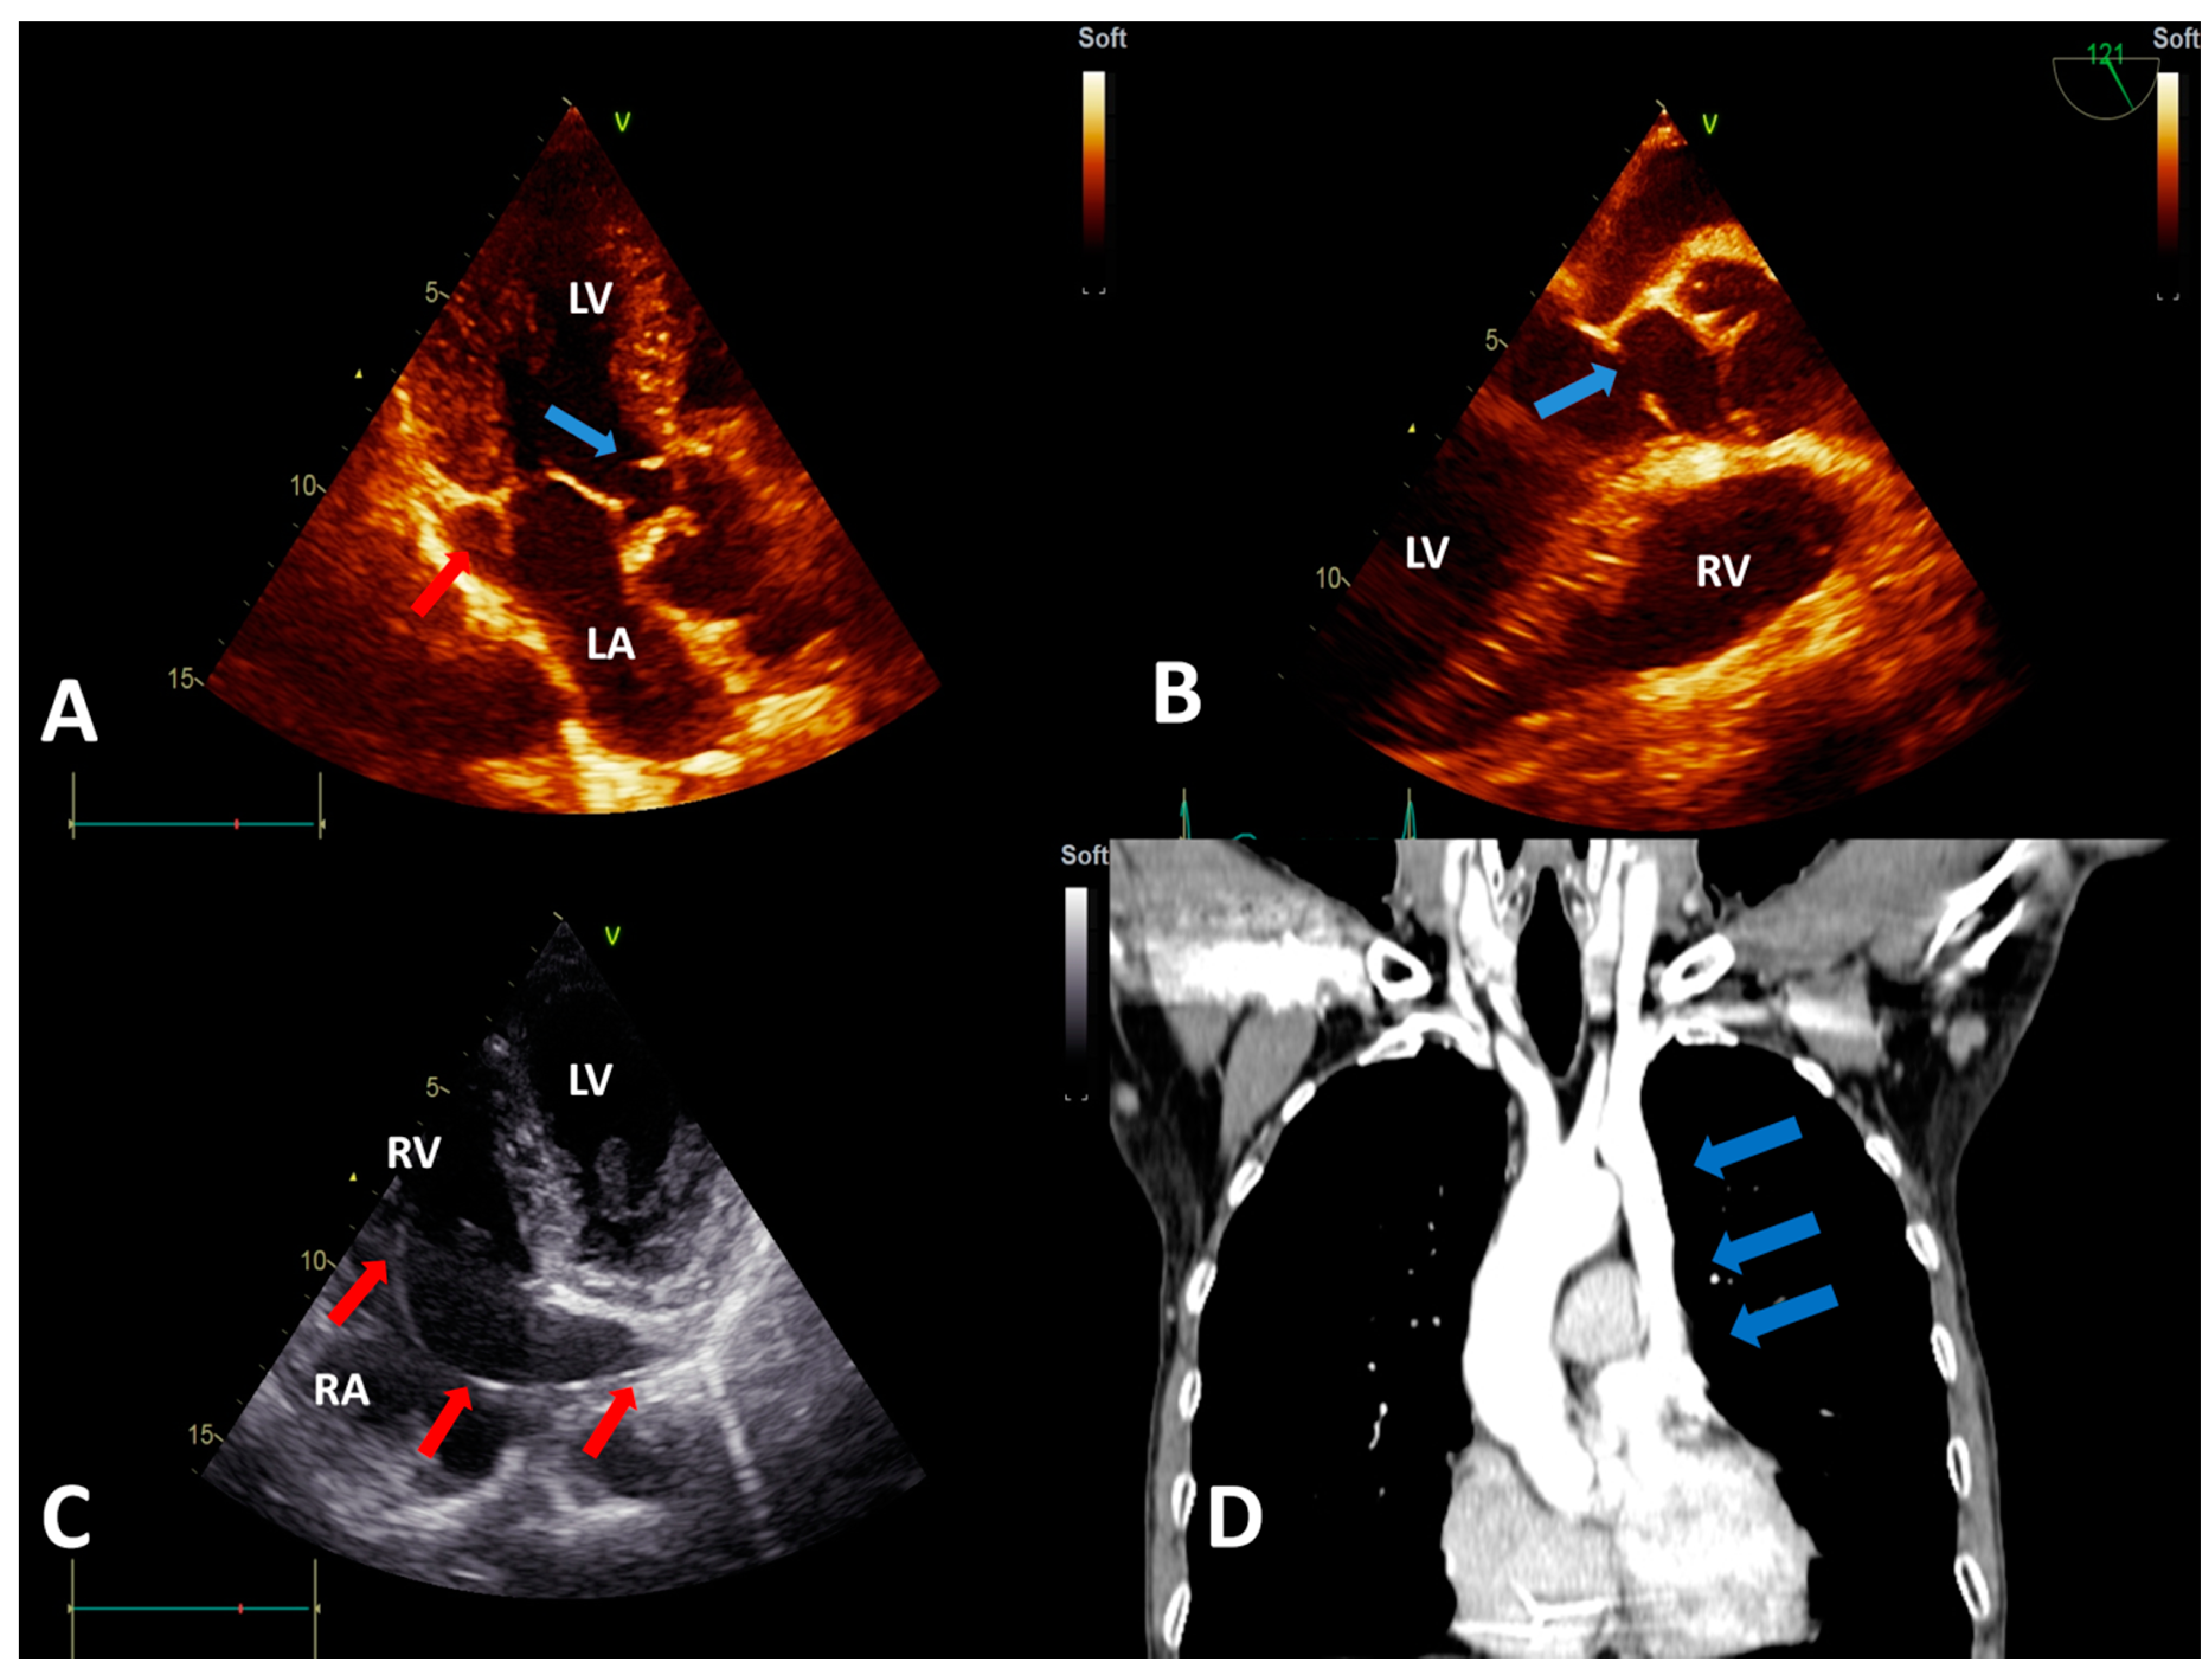

Persistent Left Superior Vena Cava with Absent Right Superior Vena Cava and Discrete Subaortic Stenosis Diagnosed in a Patient with Sick Sinus Syndrome: A Case Report and Brief Review of the Literature

2. Case Report